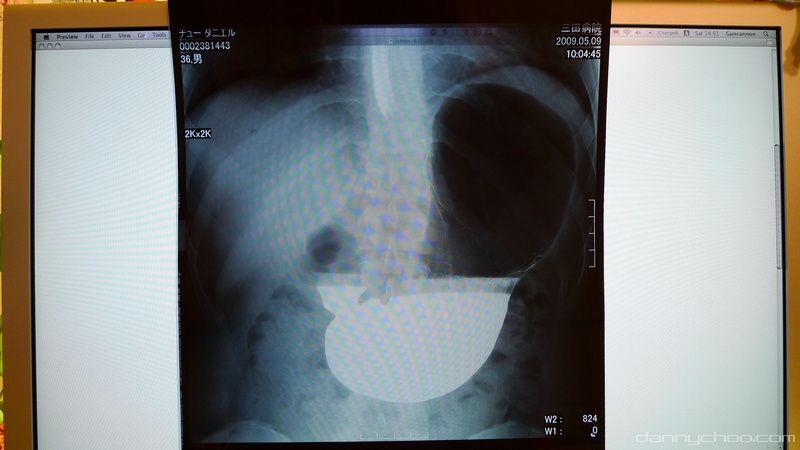

Back at home to look at my scans. The white stuff is the barium and I think that dark area is the gas. One should not eat anything before going for the tests and ends up being very hungry indeed.